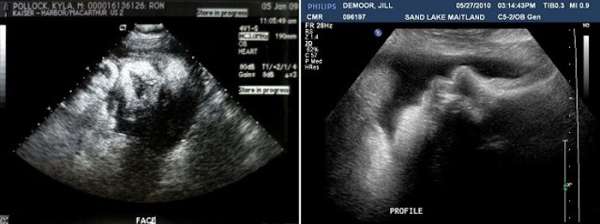

Ультразвуковое исследование (Узи)

На этом сроке плановые УЗИ уже не проводятся, на врач может назначать УЗИ для решения неотложных вопросов при планировании кесарева сечения или для решения вопроса о ведении родов. Обычно УЗИ назначают при предыдущих исследованиях с выявлением обвития пуповиной, а также для определения количества околоплодных вод, состояния плаценты, ее зрелости и расположения плода в матке, шейки матки. Также проводится и оценка развития плода, его предположительная масса рост, уточнение ПДР по данным УЗИ. Важно определить размер головки и грудки плода, длину крупных костей.

Также в 38 недель по данным УЗИ определяют размеры шейки матки, ее зрелость и состояние готовности к родам.